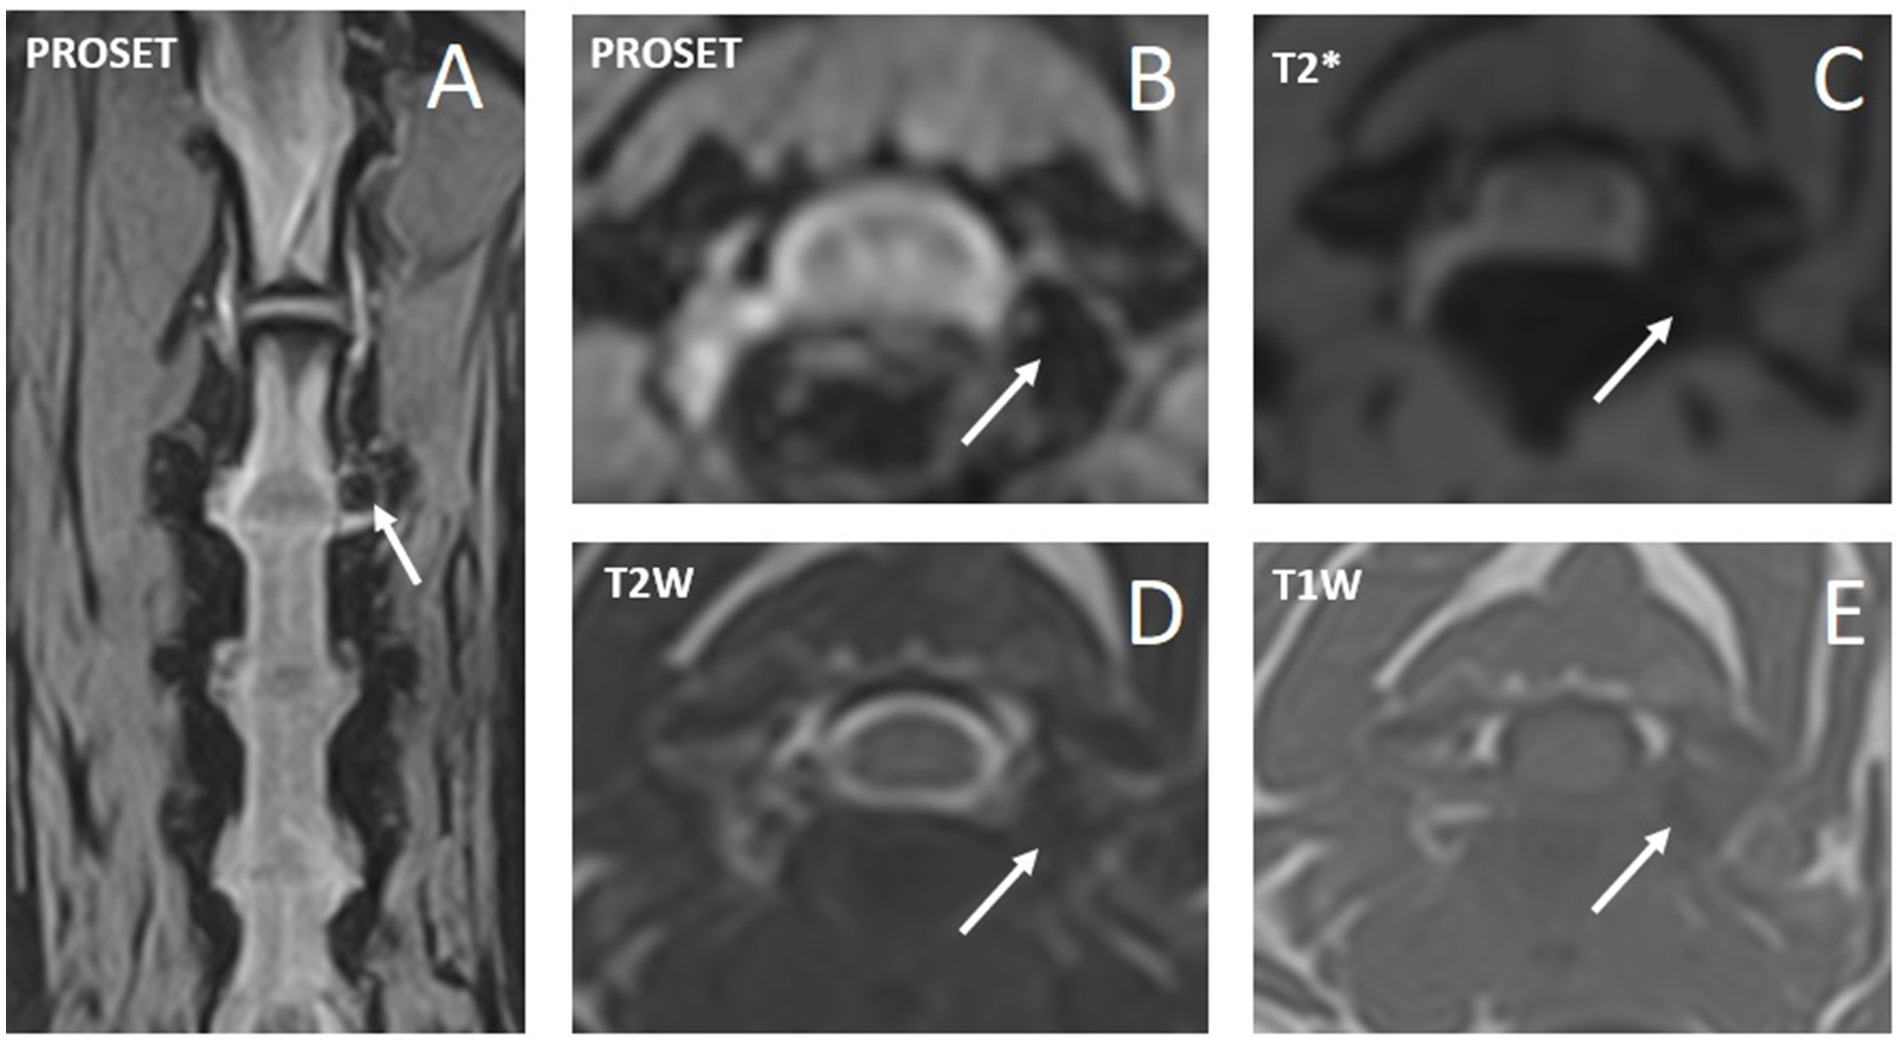

En la Tabla 2 se incluye un resumen de las modalidades de diagnóstico por imagen empleadas y los hallazgos. Las IVDE cervicales laterales lejanas se diagnosticaron con resonancia magnética de alto campo en 6/10 (60%) perros (ejemplos en las figuras 2, 3), mielograma por TC en 2/10 (20%) perros (ejemplo en la figura 4) y TC y resonancia magnética de campo bajo en 2/10 (20%) perros. Un perro (1/10, 10%) tenía un IVDE lateral lejano (C2-3, izquierda) y un IVDE lateral lejano/foraminal (C3-4, izquierda). Por lo tanto, informamos las características de 11 IVDE. Se diagnosticó IVDE lateral lejano en todos los perros (10/10, 100%); 6/11 (55%) fueron IVDE foraminales/laterales lejanos. La lateralización fue hacia la izquierda en 7/11 (64%) y hacia la derecha en 4/11 (36%) IVDEs. Todas las extrusiones laterales lejanas y la combinación de extrusiones laterales/foraminales se encontraban al nivel de un espacio IVD reducido en comparación con los espacios IVD adyacentes, y IVD parcialmente mineralizado (hiperatenuante en la TC, marcadamente hipointenso en todas las secuencias en la RM). Los espacios IVD afectados fueron: C3-4 (6/11, 55%), C5-6 (3/11, 27%) y C2-3 (2/11, 18%). A partir de las imágenes de TC, todas las extrusiones foraminales y laterales lejanas eran homogéneas y mineralizadas (hiperatenuantes a la médula espinal, HU > 500). A partir de las imágenes de resonancia magnética, las lesiones extradurales eran ligeramente heterogéneas, pero predominante y marcadamente hipointensas en todas las secuencias, compatibles con mineralización. Al comparar entre las secuencias de resonancia magnética, el material extradural fue T2W y T1W isointenso al hueso cortical, y esto resultó en una disminución de la visibilidad en las imágenes T2W en comparación con las imágenes T1W y T2*W (Figuras 1, 2). En todos los casos, la lesión extradural causó efecto de masa y la consiguiente falta de visualización de la arteria vertebral y el nervio espinal a lo largo de la longitud donde se localizó el material extradural. A partir de las imágenes de resonancia magnética, las secuencias de supresión de grasa (la mayoría de ellas STIR dorsal) revelaron una hiperintensidad leve y mal definida de los músculos epaxiales y los tejidos perineurales alrededor del material extruido. La lateralización de los signos clínicos coincidió con la lateralización de la IVDE lateral lejana (en las imágenes) en todos los casos en los que se observó lateralización.

A una hembra de 7 años de edad, un perro salchicha de 5 kg, se le presentó una historia de 2 semanas de ataques de postura cervical y vocalización anormales, que estaban disminuyendo en frecuencia, pero aún ocurrían varias veces al día (3-6 veces, 10-60 s cada una). Los videos proporcionados por el propietario mostraron fasciculaciones de los músculos cervicales y pseudodistonía cervical con ventroflexión e inclinación/giro de la cabeza (tortícolis) (Video complementario S1). No se escuchó ninguna vocalización en los videos ni fue reportada por los propietarios. El examen clínico general no presentaba presentaciones. El examen neurológico no fue notable y, en particular, no se observaron signos de hiperestesia cervical a la palpación. El perro fue capaz de sacudir la cabeza con vigor después de infundir una gota de agua en el canal auditivo externo (prueba de gota en el oído). Esta prueba es utilizada frecuentemente por uno de los autores (KS) para evaluar la capacidad de realizar un movimiento normal y vigoroso de sacudida de la cabeza. La vacilación, el rendimiento incompleto o la aparición de signos de dolor (vocalización) cuando el perro (intenta) exhibir este comportamiento se interpreta como anormal. La resonancia magnética de alto campo reveló una IVDE lateral y foraminal C3-4 del lado izquierdo (Figura 2). El tratamiento se inició con meloxicam (0,1 mg/kg cada 24 h durante 2 semanas) y gabapentina (10 mg/kg cada 8 h durante 2 semanas, seguido de cada 12 h durante 1 semana y luego discontinuizado). Se informó de un ataque recurrente en los primeros 2 días de tratamiento, posteriormente no se observó recurrencia. El seguimiento total fue de 10 meses sin recidiva de los signos.

En nuestro estudio, 10 perros tenían 11 IVDEs: 6/11 eran IVDE combinados far-lateral/foraminal y 5/11 eran IVDE pura far-lateral (es decir, el material extruido se localizaba distal al foramen, lateral al IVD). Las IVD laterales lejanas en perros se han descrito con mayor frecuencia en la zona toracolumbar, afectando principalmente a las IVD lumbares caudales (L5-6 y L6-7) (7). La falta de publicaciones sobre las IVED cervicales en extremo sugiere que rara vez se diagnostica. El conocimiento de este tipo de IVDE sigue siendo de vital importancia para los clínicos, especialmente para aquellos que realizan e interpretan estudios de diagnóstico por imagen. Todas las extrusiones de disco foraminal/far-distal incluidas en este estudio estaban mineralizadas y estaban al nivel de un espacio de disco intervertebral estrecho con un disco intervertebral parcialmente mineralizado. Dado que las lesiones mineralizadas y las estructuras óseas se evalúan bien a partir de las imágenes de TC, estas lesiones eran obvias y se diagnosticaban fácilmente mediante TC. La mineralización puede ser más difícil de describir a partir de estudios de resonancia magnética y, por lo tanto, cuando se sospecha una extrusión de disco foraminal/distal lejano, es importante incluir varias secuencias y varios planos.

• Incluir T2W sagital y T1W sagital para visualizar un disco mineralizado intervertebral estrechado (hipointenso en T2W e hipointenso en T1W).

• Secuencias de supresión de grasa dorsal (como STIR, DIXON), con el fin de evaluar cualquier intensidad de señal anormal lateralizada de los tejidos paravertebrales y perineurales.

• T2W, T1W y T2* transversales a nivel de los forámenes sospechosos/extrusión distal lejana desde el nivel del cuerpo medio de la vértebra craneal hasta el cuerpo medio de la vértebra caudal con respecto al espacio de interés IVD. Un IVD de interés puede definirse como cualquier IVD que muestre características de señal consistentes con la degeneración (p. ej., T2-hipointensidad del núcleo pulposo). La combinación de estas tres secuencias ayudará a visualizar con precisión el material del disco extruido y corroborar la mineralización (hipointensa en todas las secuencias, mejor representada en T2*). Estos planos transversales permitirán la evaluación de los nervios espinales y las arterias vertebrales.

• Seleccione el grosor de corte adecuado, idealmente 2,5 mm cuando utilice las secuencias anteriores.

• Se pueden agregar imágenes PROSET (excitación de agua) para evaluar más a fondo los nervios espinales y evaluar su tamaño y curso.